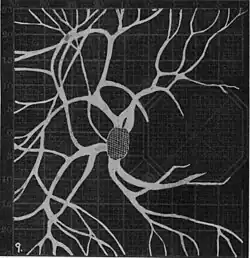

Angioscotomas were first discovered and mapped out by John Norris Evans (1891-02-28--1953-04-08)[2] in 1926, who coined the term angioscotometry to describe the painstaking charting of the scotoma of the retinal blood vessels by manual perimetry. He seated each subject in a seat in a dark setting, and tested whether they could see a tiny bright test object placed at various locations.[3] Using a 1.5 mm white disk, Evans reported intricate branch‑like scotomas that mirrored the arteries and veins emerging from the optic disc, with a full map requiring up to 2 hours to complete. He plotted this for subjects under various conditions, such as while holding breath, with glaucoma, etc. A year later, he confirmed that only short stump‑like scotomas had been noticed previously, some further data plotted with a smaller 1 mm stimuli, and under varying conditions on the subject.[4] He published a monograph on this in 1938 in which he described its use in assisting diagnosis of various conditions, such as retinal edema, glaucoma, optic neuritis, etc.[5]

In the 1940s there were further developments. Evans reviewed the state of research in 1942.[6] In 1945, Welt designed a portable campimeter and linked the size of both the blind spot and the angioscotoma to retinal arterial pressure.[7] In the same year, Weekers and Humblet published detailed tracings that overlaid vessel photographs onto Bjerrum screen plots, firmly establishing the one‑to‑one correspondence between vascular anatomy and scotoma shape.[8]

20. Venous engorgement. 21. After pressure over internal 22. Same case, normal. 23. Scotoma after ligation of common carotid. 24. Edematous swelling of nerve and retina. 25, Normal blind spot of other eye. -